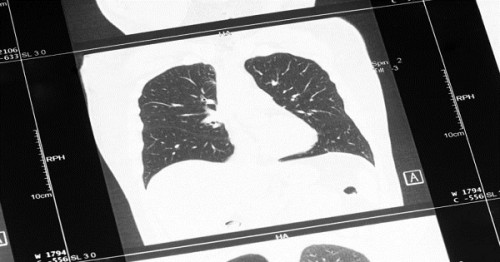

Nguyên nhân đứng thứ 3 gây tử vong trên toàn thế giới là COPD, còn gọi là bệnh phổi tắc nghẽn mãn tính. Đây là một khái niệm dùng để chỉ các bệnh tiến triển ở phổi, ví dụ như khí phế thũng, viêm phế quản mạn tính và hen suyễn dai dẳng. Triệu chứng phổ biến của bệnh COPD là khó thở, khò khè và ho nhiều.

Viêm đường hô hấp dưới là một nhóm bệnh, bao gồm cả bệnh viêm phổi. Viêm phổi có nguyên nhân là do nhiều loại vi sinh vật, vi khuẩn và virus gây ra. Viêm phổi có thể gây tử vong rất nhanh, đặc biệt là ở người cao tuổi. Viêm đường hô hấp dưới cũng là bệnh truyền nhiễm gây tử vong hàng đầu, gây ra khoảng 3 triệu ca tử vong trên toàn thế giới vào năm 2016.

Ung thư khí quản, phế quản và ung thư phổi gây ra khoảng 1.7 triệu ca tử vong vào năm 2016. Ung thư phổi đặc biệt là bệnh ung thư gây tử vong hàng đầu ở Mỹ, ở cả nam gới và nữ giới. Mặc dù ung thư phổi có liên quan đến tình trạng hút thuốc lá, nhưng kể cả những người không hút thuốc cũng có nguy cơ bị ung thư phổi. Đa số các bệnh ung thư đường hô hấp sẽ có cùng các triệu chứng, ví dụ như khò khè và khó thở.